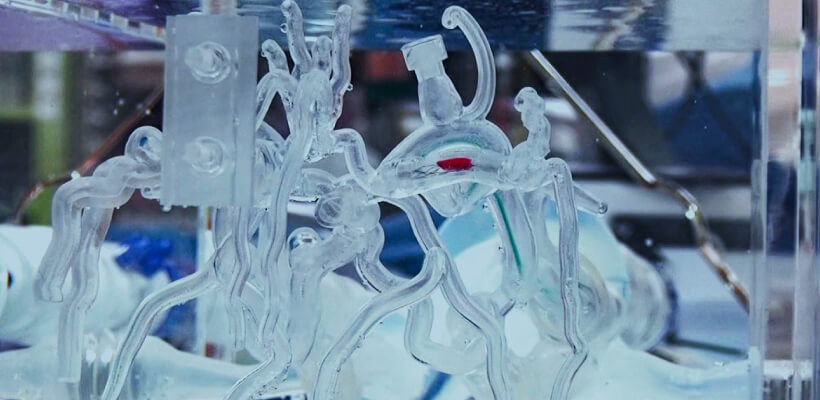

Vascular IVR

Products

- 3D printing